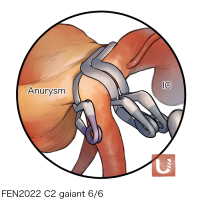

FEN2022シリーズ